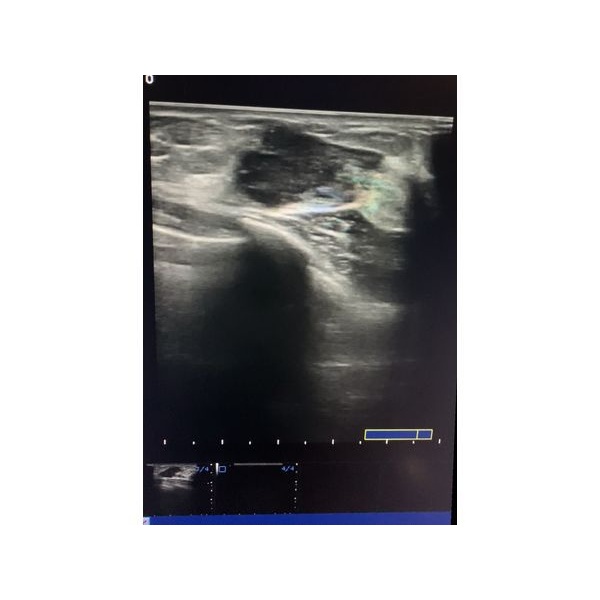

УЗИ обнаружило образование неправильной формы с чётким неровным контуром. Внутри отмечались гиперэхогенные включения с усиленным кровотоком. Эти результаты позволили заподозрить у пациентки злокачественную опухоль. В подмышечном лимфоузле предположительно находился метастаз.